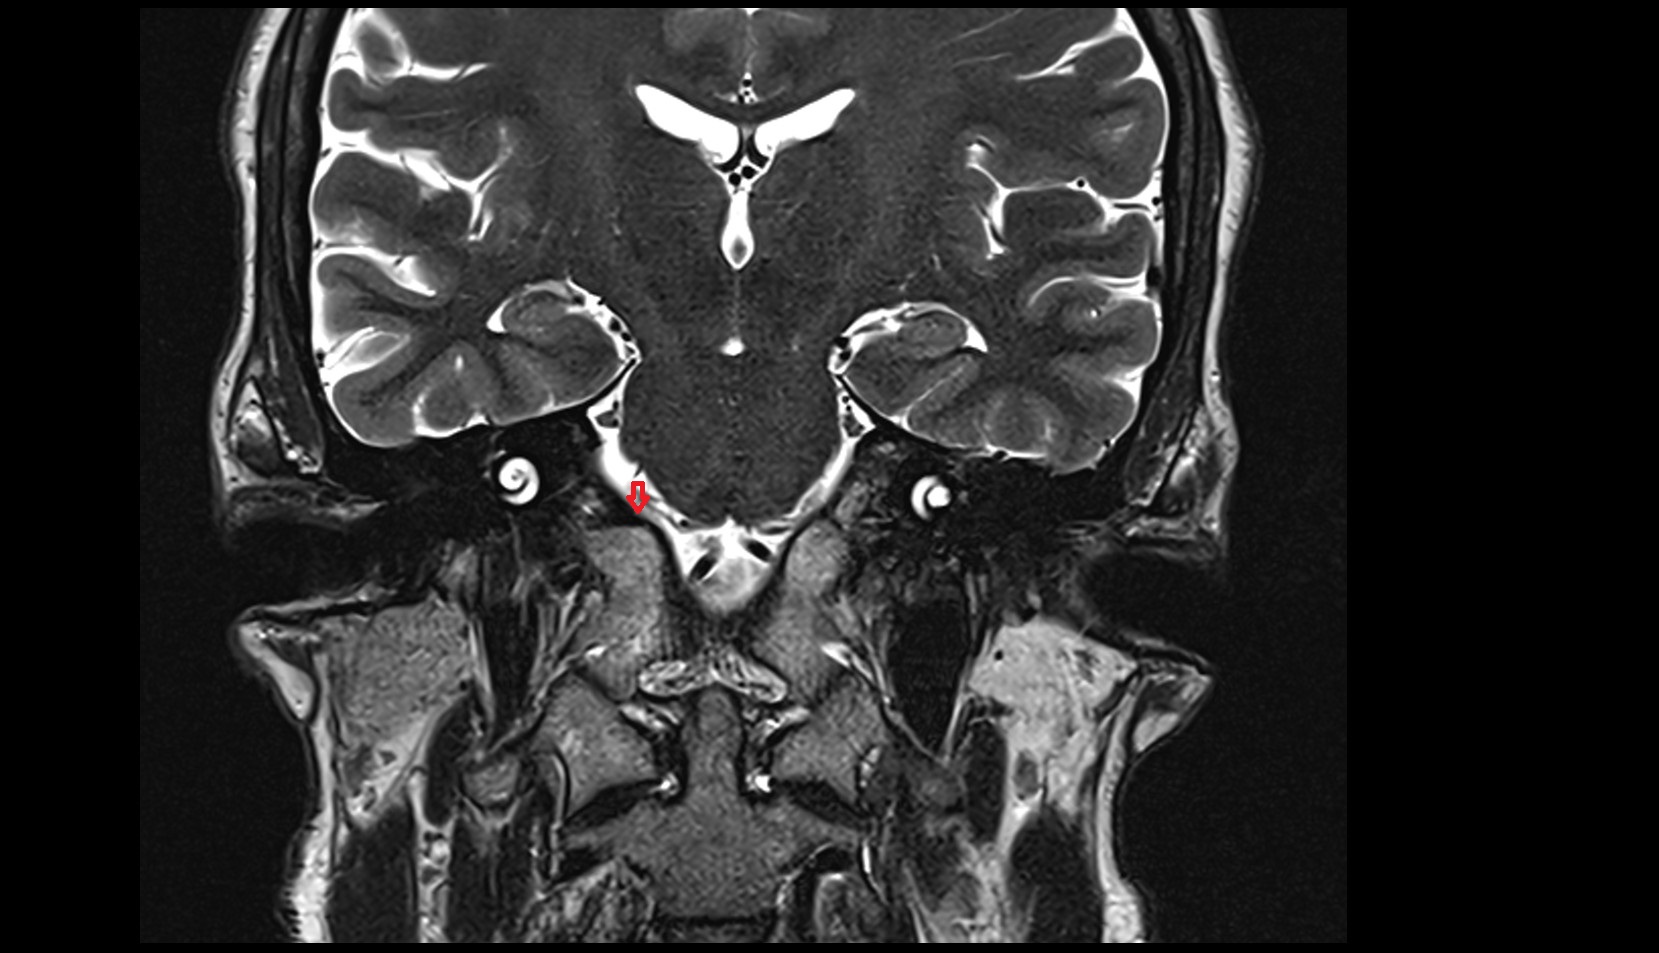

- Abducens nerve (Cranial nerve VI)

- Meckel’s cave (Trigeminal cave)